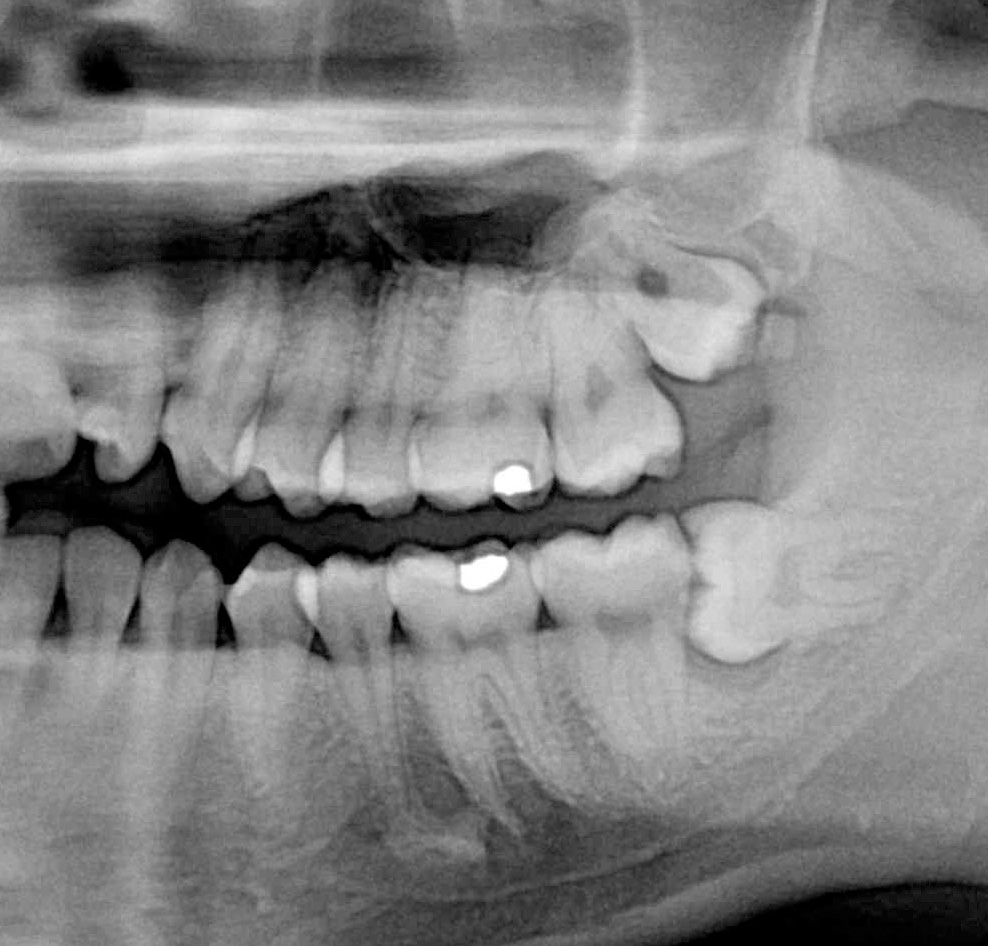

NewTom Giano

Jedná se o nejnovějším přístroj ze skupiny dentálních hybridních CBCT (3D) + 2D (pan i ceph) systémů. Opět umožňuje na základě jediného snímkování vytvořit všechny typy RTG zobrazení, které jsou pro lékaře potřebné. Používaná technologii tzv. „kuželového paprsku“ a speciální senzory pro minimální zátěž při snímkování pacienta.

Vyšetření pomocí tohoto přístroje (nebo 3D DVT - NewTom) a získaná data používáme pro každou implantaci, dále ve stomatochirurgii (zlomeniny čelistí, zuby moudrosti, cysty, onemocnění čelistního kloubu), ortodoncii (retinované zuby, nadpočetné zuby), parodontologii atd.